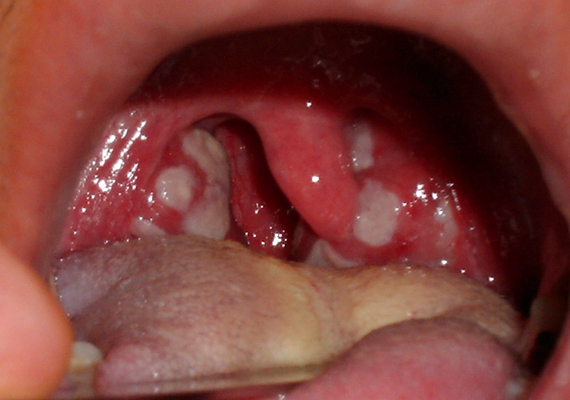

扁桃體週膿腫圖片